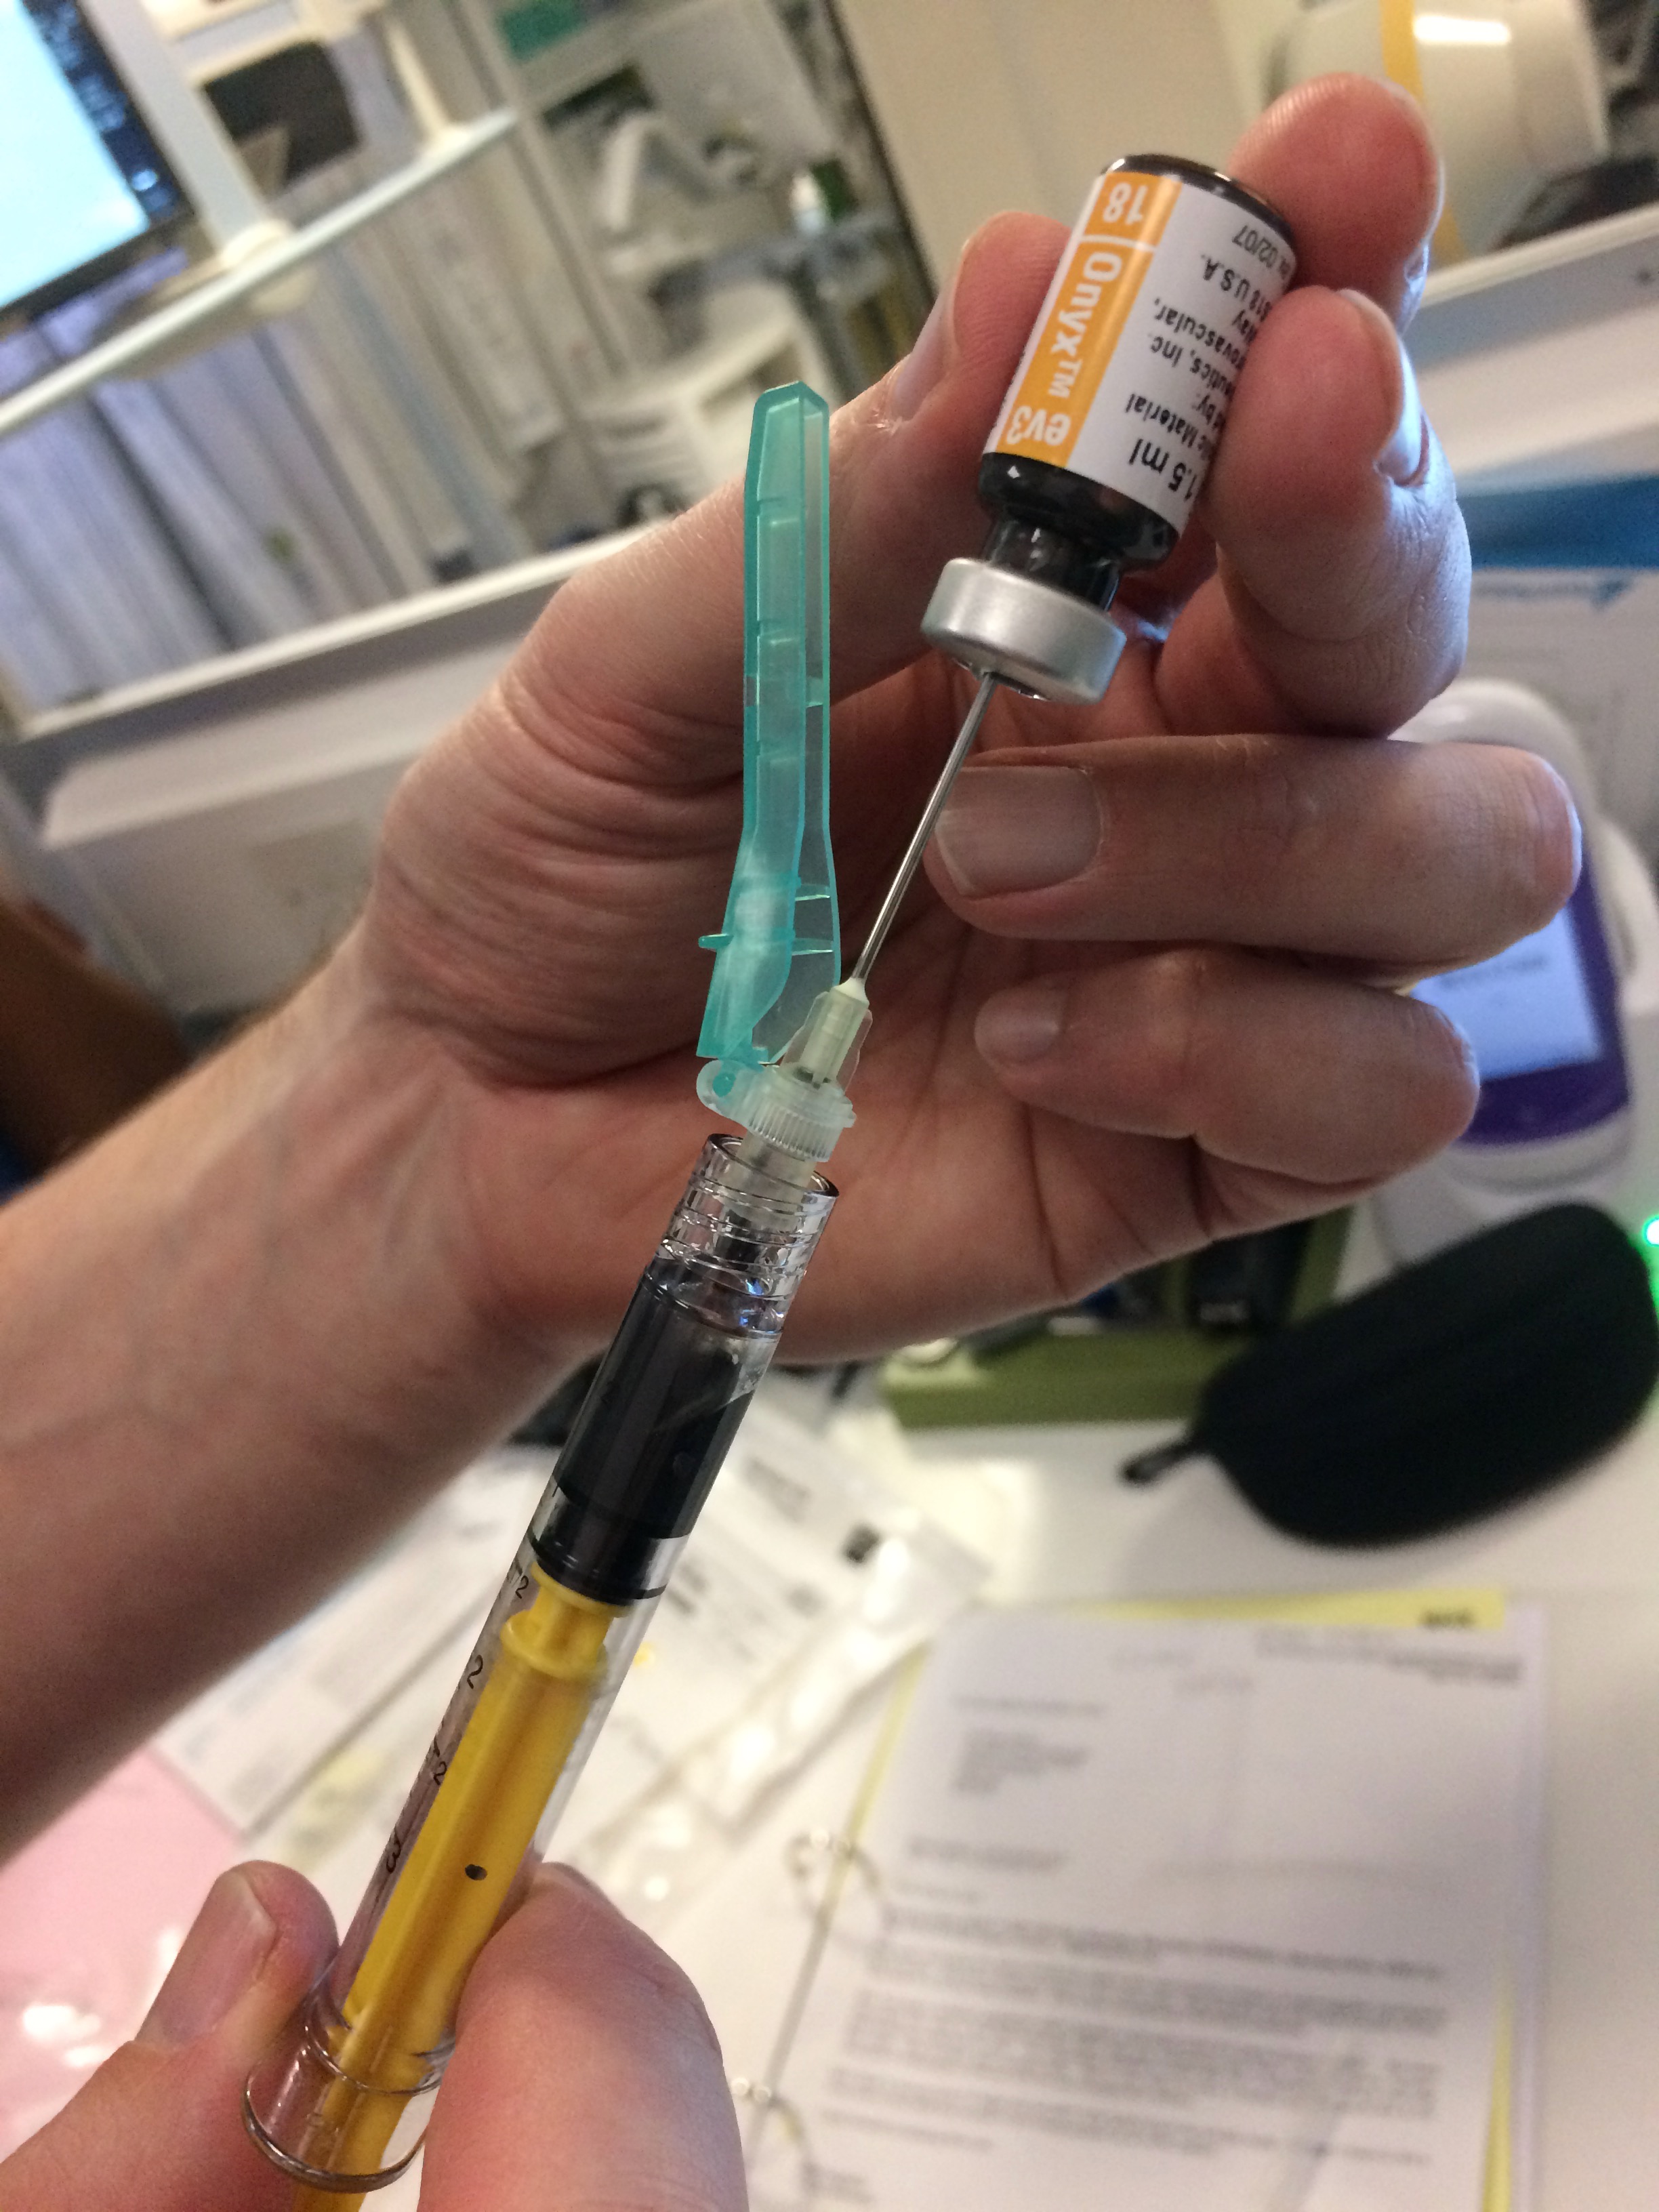

The research and work followed the treatment of tangled blood vessels in the brain, or arteriovenous malformations, through an embolisation procedure performed by the Neuroradiology team at Western General Hospital’s Department of Clinical Neuroscience. In this process, a glue-like substance is introduced into the brain which changes the smell of the breaths of both neuroradiologist and patient. As there is no “opening-up” of the body, the procedure leaves no visible scars and this so-called “Onyx smell”, which lingers in the wards after the intervention, is the only physical indicator of the operation that took place.

The main molecule responsible for this odour is also a key component in the smell of so-called “carrion flowers” and other vegetable bodies.